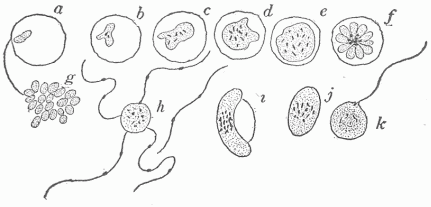

- Classification Of The Organisms Which Cause Disease.—Bacteria: Size, Shape, Structure, Capacity For Growth, Multiplication And Spore Formation.—The Artificial Cultivation Of Bacteria.—The Importance Of Bacteria In Nature.—Variations In Bacteria.—Saprophytic And Parasitic Forms.—Protozoa.—Structure More Complicated Than That Of Bacteria.—Distribution In Nature.—Growth And Multiplication.— Conjugation And Sexual Reproduction.—Spore Formation.—The Necessity For A Fluid Environment.—The Food Of Protozoa.—Parasitism.—The Ultra-Microscopic Or Filterable—Organisms.—The Limitation Of The Microscope.—Porcelain Filters To Separate Organisms From A Fluid.— Foot And Mouth Disease Produced By An Ultra-Microscopic Organism.— Other Diseases So Produced.—Do New Diseases Appear?

Fig. 12.—The Various Cells In The Blood. (a) The red blood cells, single and forming a roll by adhering to one another; (b) different forms of the white blood cells; those marked "1" are the most numerous and are phagocytic for bacteria.

The blood consists of a fluid, the blood plasma, in which numerous cells are contained. The most numerous of these are small cup-shaped cells which contain a substance called hæmoglobin, to which the red color of the blood is due. There are five million of these cells in a cubic millimeter (a millimeter is .03937 of an inch), giving a total number for the average adult of twenty-five trillion. The surface area of all these, each being one thirty-three hundredth of an inch in diameter, is about thirty-three hundred square yards. The hæmoglobin which they contain combines in the lungs with the oxygen in the inspired air, and they give up this indispensable substance to the cells everywhere in the body. There are also eight thousand leucocytes or colorless cells in a cubic millimeter of blood, this giving a total number of four billion in the average adult, and these vary in character and in relative numbers (Fig. 12). The most numerous of these are round and slightly larger than the red cells; they have a nucleus of peculiar shape and contain granules of a definite character. These cells serve an important part in infectious diseases in devouring and destroying parasites. They have power of active independent motion and somewhat resemble certain of the free living unicellular organisms. The blood plasma, when taken from the vessels, clots or passes from a fluid into a gelatinous or semi-solid condition, which is due to the formation within it of a network of fine threads termed fibrin. It is by means of the clotting of the blood that the escape of blood from ruptured vessels is arrested.